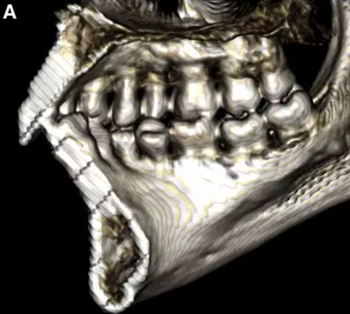

然而,CBCT成像也具有較大的限制:有限的分辨率,牙體組織的不準確表現(xiàn),以及當患者在咬合位或者完全牙尖交錯位CBCT掃描時,上頜骨和下頜骨牙齒之間發(fā)生的混合(圖1)。 這種混合使上頜骨與下頜骨牙齒的自動分離復雜化,并且由于咬合解剖結構和細節(jié)的不準確而使人工分離變得困難。

圖1. 在CBCT中咬合時上頜牙齒和下頜牙齒咬合面的混合和咬合細節(jié)的喪失。